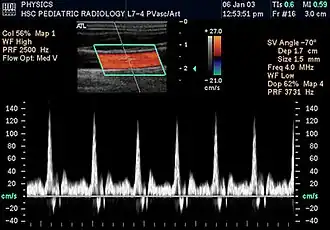

Colour Doppler shows the direction of the blood flow in red or blue (either towards or away from the transducer). Meanwhile, spectral Doppler not only shows the direction of blood flow, it also shows the phases (pulsatility) and acceleration of the blood flow. Any sudden changes in direction of blood flow produces audible sounds on the ultrasound machine.[3]

In spectral Doppler, the y-axis shows the direction and velocity of the flow. Meanwhile, the x-axis (as known as "baseline") shows the flow over time. The gradient at any point on the waveform would therefore shows the acceleration of the flow. In "antegrade" flow, the blood flows according to the normal flow within the circulatory system (e.g. veins flow towards the heart while arteries flows away from the heart). In "retrograde" flow, the flow would reverse (e.g. veins flow away from heart or arteries flow towards the heart). However, "retrograde" flow can be both abnormal or normal. For example, in portal hypertension, there is an abnormal portal venous flow where it flows away from the liver (hepatofugal flow) instead of the normal flow towards liver (hepatopetal flow). In jugular venous pressure waveform of the internal jugular vein, the retrograde "a" waveform is a normal flow due to right atrium contraction. Both antegrade or retrograde flow can be either towards or away from the probe transducer, depending on the position of the probe relative to the blood flow. Blood flow toward the transducer would appear above the baseline while blood flows away from the transducer will appear below the baseline. Waveform of the flow can be classified as: pulsatile (as in arteries), phasic (as in veins), non-phasic (as in diseased veins), and aphasic (no flow). Spectral broadening (thickness of the waveform) increases from large vessels (plug flow) to medium vessels (laminar flow) to small/stenotic/diseased vessels (turbulent flow) due to a larger variety of blood with different ranges of velocities in those with turbulent flow.[3]

Upstream and downstream stenosis refers to the location of the stenotic site relative to the ultrasound probe. Upstream stenosis means the location of stenosis is located before the ultrasound probe. It causes a marked decrease in peak systolic velocity when compared to end-diastolic velocity, causing marked reduction in resistance index. Meanwhile, downstream stenosis is located after the ultrasound probe. Thus, there is only a slight reduction in peak systolic velocity and end-diastolic velocity (where end-diastolic velocity is reduced more than peak systolic velocity), resulting in an increased resistance index.[3]